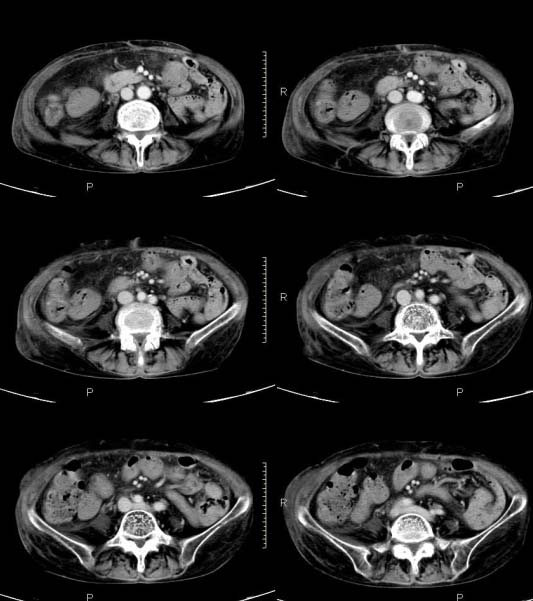

女,71岁,腹痛、腹胀、黄疸20余天,b超示肝内外胆管高度扩张内伴絮状物质(未提示梗阻部位或结石影),经抗炎解痉治疗后,肝功能有所好转,但胆道梗阻状态并未减轻。患者曾于1970年代做过胆囊切除术,1997年因胰腺炎而手术;且患者有糖尿病10余年。ct图片传了静脉期,未传动脉期了,最后一序列为3.2mm薄扫,请各位同仁仔细看看,确定一下胆管梗阻的部位,是炎性梗阻还是肿瘤性梗阻,是否与胰腺炎有关系,扩张胆总管中段前缘是否是胰管。请高手们最好用图示来指出梗阻部位。

扩张的胆管直达胰头,但胰头增大又不明显,且无异常密度影。考虑壶腹部占位。

请大家看看扩张的胆总管内见一弧线形间隔,怎样解释?

先天性胆总管囊肿伴肝内外胆管扩张!

肝内外胆管显著扩张,考虑先天性胆管囊肿(ⅳ型)。

肝内胆管远侧、近侧不比例扩张,以近侧为明显。胆总管扩张。考虑先天性胆管囊肿(ⅳ型)。